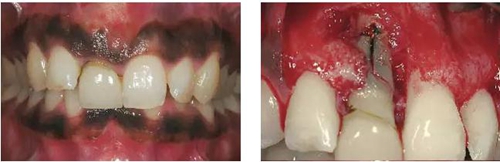

圖1、該病例顯示了厚齦生物型和中弧線形齦乳頭形態(tài)。右上中切牙由于牙根縱裂而需要拔除。由于該患牙伸長,使得軟組織量垂直向增加。牙齦色素沉著是個(gè)美學(xué)挑戰(zhàn)。

圖2、翻開全厚瓣可見明顯的牙根縱裂,唇側(cè)骨板2/3受到累及而缺損。